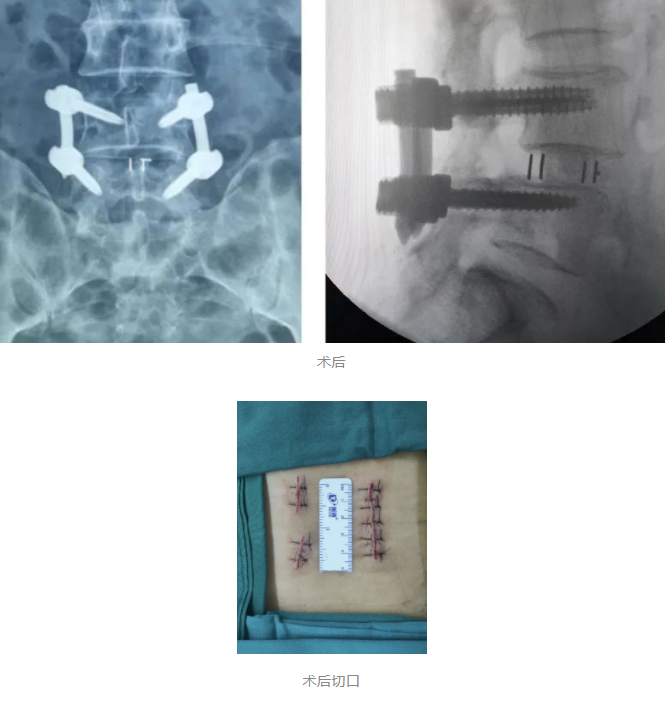

入院后,在完善相关检查后王阿姨被诊断为:腰椎管狭窄、腰椎不稳、腰椎间盘突出。随后脊柱外科尚军、张冶手术团队在骨科机器人+3D裸眼显微镜的辅助下,为王阿姨进行了腰椎后路减压+内固定+椎间融合术 (L4/5)。

在骨科机器人+3D裸眼显微镜的辅助下,王阿姨的手术进行的很顺利,术中仅出血约50ml,而皮肤表面也只留下了3cm的小切口,这一切都与传统手术形成的极大对比!可以说,骨科机器人+3D裸眼显微镜在当今脊柱外科关于微创手术这一概念中,已成为一种趋势,其最大程度的保证了患者在术中的安全,将微创手术最为核心的精准、伤害小的特点发挥的淋漓尽致,这对于患者本身及术后的康复来说都极为有利!